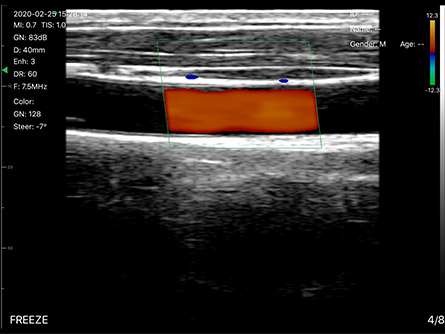

- 显示模式:B、B/M,彩超版本有CF、PW、PDI

彩超(白色头192阵元/藏蓝头128阵元)、高配黑白(浅蓝头128阵元)、低配黑白超(灰头80阵元)

7.5/10MHz(声头40mm宽)、10/14MHz(声头25mm宽),和带导针架固定装置的PICC专用等型号

穿刺/介入引导:甲状腺消融、颈静脉穿刺、锁骨下静脉穿刺、颈神经丛/臂神经丛麻醉神经阻滞、贵要静脉置管PICC、腰椎穿刺、桡静脉等注射、经皮肾手术引导、血透置管/血栓监测、人流清宫、胆管穿刺/手术、关节积液抽取、疼痛治疗引导、美容整形可视引导、导尿引导

日常检查:甲状腺、乳腺、脂肪肝/肝硬化、盆底盆腔、前列腺、脑卒中筛查、眼球视网膜动脉、子宫及附件、卵巢卵泡监测、查环查孕、胎儿扫查、肌骨、足底、骨折判断、静脉曲张、肝肾脾、膀胱/泌尿功能、尿量测算等